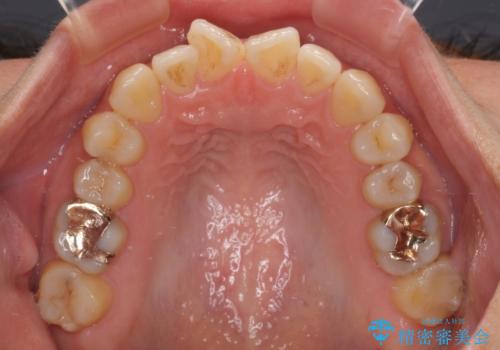

- 下顎小臼歯が欠損しており、さらに上顎が全体的に突出していることを気にして来院された患者様です。

下顎は片方の小臼歯が欠損していたため、正中がずれた上に、上下前歯が接触していない状態でした。

上顎左右の小臼歯2本および下顎小臼歯を1本抜歯し、補助装置を用いて上顎大臼歯が前方に移動しないように固定した上で、ワイヤー装置にて矯正治療を行うこととしました。